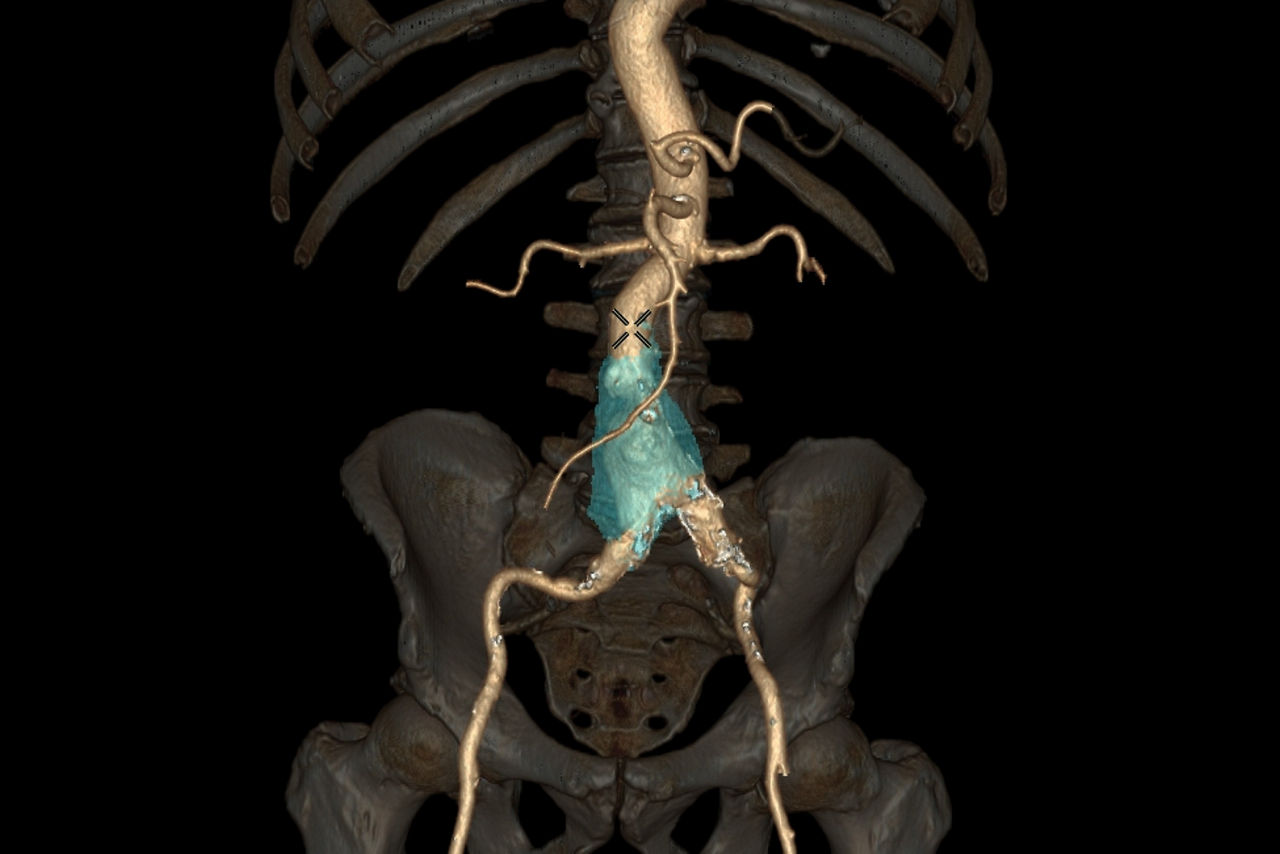

Autobone & VesselIQ Xpress

Fast and efficient vessel analysis from CT Angiography exams.

• Thrombus detection with measurements and comparison over time.